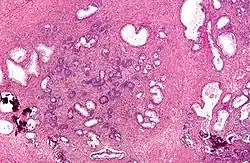

![]() Micrograph of a transurethral resection of the prostate (TURP) specimen, showing BPH (nodular hyperplasia of the prostate) – left-of-center in image. H&E stain. | |

Transurethral resection of the prostate (commonly known as a TURP, plural TURPs, and rarely as a transurethral prostatic resection, TUPR) is a urological operation. It is used to treat benign prostatic hyperplasia (BPH). As the name indicates, it is performed by visualising the prostate through the urethra and removing tissue by electrocautery or sharp dissection. It has been the standard treatment for BPH for many years, but recently alternative, minimally invasive techniques have become available.[1] This procedure is done with spinal or general anaesthetic. A triple lumen catheter is inserted through the urethra to irrigate and drain the bladder after the surgical procedure is complete. The outcome is considered excellent for 80–90% of BPH patients. The procedure carries minimal risk for erectile dysfunction, moderate risk for bleeding, and a large risk for retrograde ejaculation.[2]